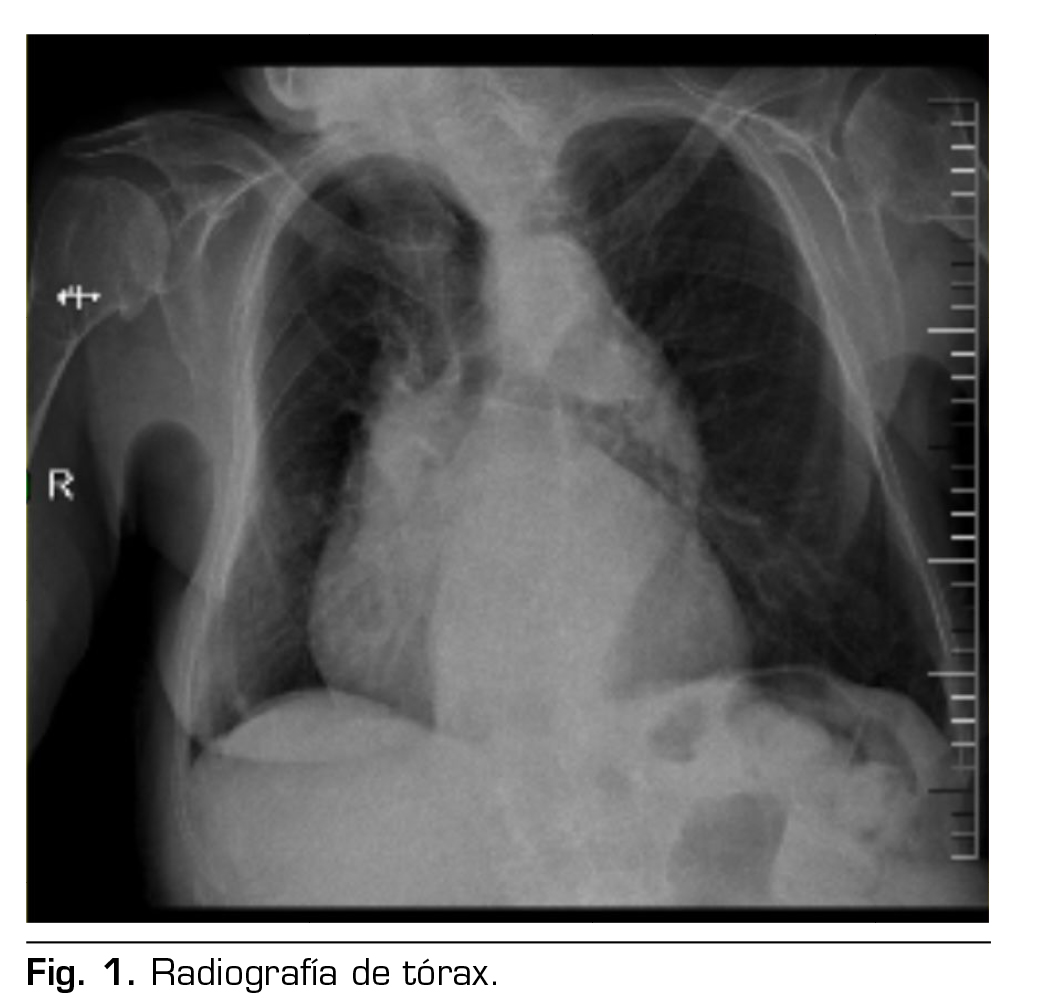

Presentación de caso: Presentamos el caso clínico de un paciente adulto mayor de 88 años ASA III, sometido a una hernioplastia inguinal electiva, bajo anestesia regional: bloqueo II/IH bajo guía ecográfica más sedación, manejo analgésico complementario con paracetamol y antinflamatorios, alta de cirugía médica ambulatoria a su domicilio y control postoperatorio sin complicaciones.

Figura 1